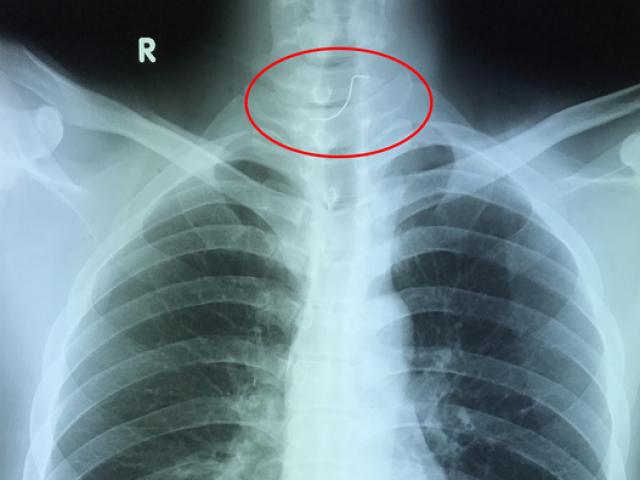

Mũi khoan nằm trong dạ dày bệnh nhân

Cuối cùng chị gọi điện thoại hỏi ý kiến một người bạn là bác sĩ, và được khuyên nên đi kiểm tra, bởi cơn đau chị gặp phải dù không lớn nhưng có thể là biểu hiện nên nghi ngờ đến dị vật. Kết quả chụp X-quang cho thấy, có vật bằng kim loại nhỏ trong dạ dày bệnh nhân nên các bác sĩ quyết định thủ thuật nội soi để lấy dị vật.

BS Nguyễn Hữu Tiếng, Phó trưởng khoa Tiêu hóa, Bệnh viện An Bình, kể lại: hình ảnh nội soi cho thấy trong dạ dày bệnh nhân là một mũi khoan nhọn dài đến 3cm và đã gây một số tổn thương cho dạ dày. Quá trình lấy ra khá khó khăn và phải nhờ đến một dụng cụ chuyên dụng, trùm phần nhọn của mũi khoan lại khi đi qua đoạn hẹp của thực quản. Cuối cùng, ê kíp thủ thuật cũng loại bỏ thành công dị vật. Theo BS Tiếng, may mắn là bệnh nhân đã quyết định đi kiểm tra sớm, bởi dị vật nhọn và nguy hiểm như mũi khoan nếu để đi vào ruột non sẽ cực kỳ nguy hiểm, có thể gây thủng ruột, và hậu quả xấu nhất là gây áp xe, viêm phúc mạc… đưa đến nguy cơ tử vong.